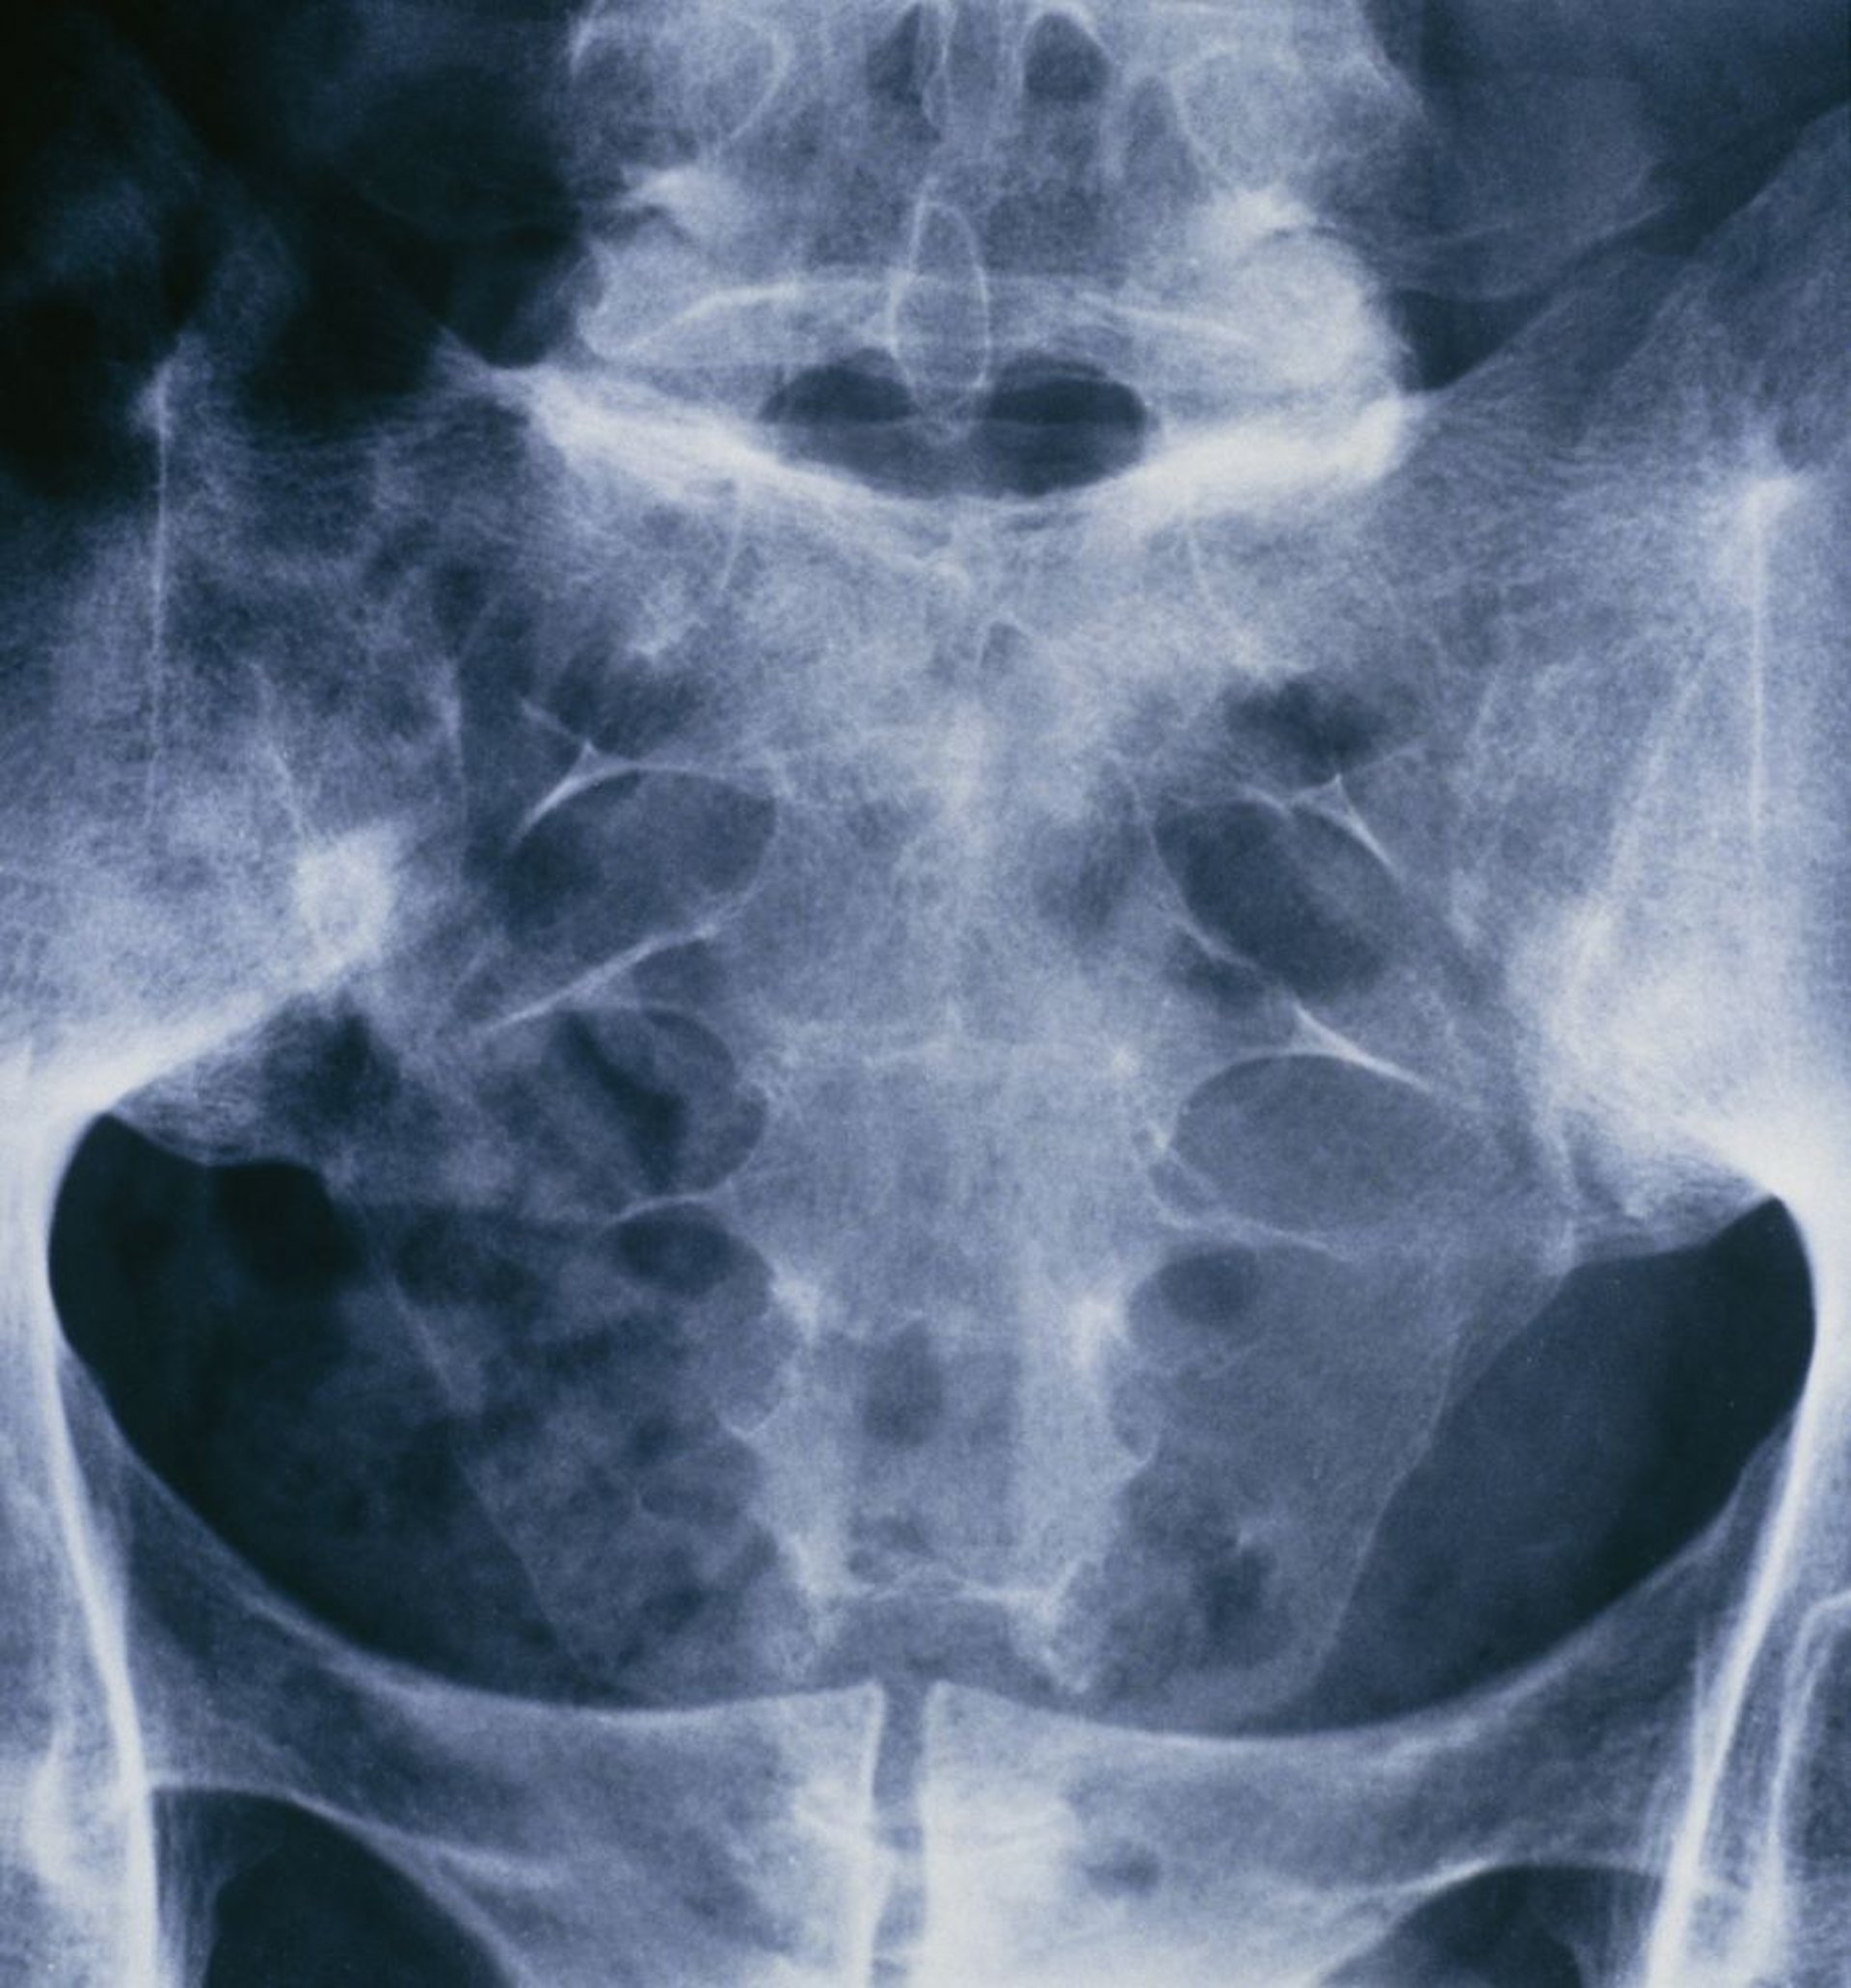

Анкилозирующий спондилит (сакроилеит)

Этот рентгеновский снимок таза и крестцового отдела позвоночника человека, страдающего анкилозирующим спондилитом, демонстрирует слияние обоих крестцово-подвздошных суставов.